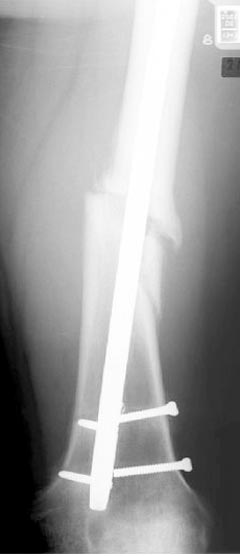

Лечение бедра - ургентное оперативное лечение антеградным с минимально рассверливанием, фиксацией с минимальным диаметром штифта и плюс irrigation and debridment и с закрытием поперечной до 10 см раны на уровне перелома в день поступления.

После трех дней начались выделения из ран которые промывалась в палате и рана постепенно закрылась в течение нескольких месяцев. Эмпирически получал 6 недельний курс антибиотика Vancomycin внутривенно.

Снимки представлены: 1 мес; 3 мес; 1 год; 2 года, предоперационные и ротационная КТ грамма